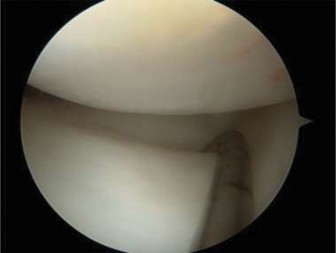

The correct answer is (B). If the patient were asymptomatic, then the discoid meniscus could simply be observed with a return to unrestricted sporting activity. For a younger patient who is intermittently symptomatic and/or elects to not undergo operative intervention, lateral compartment unloader bracing may be appropriate until the patient and/or family agree to intervention. Long-leg casting is not appropriate and will do nothing more than cause stiffness, loss of strength, and range of motion. As the patient is symptomatic, has mechanical symptoms, and has potential tearing seen on MRI, arthroscopic intervention is indicated to examine the meniscus and intervene. The patient is taken to surgery, and intraoperative images ( Figs. 10–31 and 10–32 **) are shown. The next step in management is:**

Figure 10–31

Figure 10–32

Discussion

The correct answer is (C). The arthroscopic images demonstrate a complete discoid meniscus which is covering the entire lateral tibial plateau. As the patient is symptomatic from the meniscus, saucerization is the first step in management. The meniscus is trimmed back using a combination of shavers and biters to a stable peripheral rim, which replicates the width of the native meniscus. Complete meniscectomy would not be indicated in a patient of this age due to the high risk of early onset degenerative arthritis. In fact, even prior to intervention, many discoid menisci have been associated with the development of lateral hemijoint osteochondral lesions. Although chondroplasty may be necessary, the meniscus is the underlying problem causing chondral wear and must be dealt with first. After saucerization is performed, the meniscus is probed and the following arthroscopic image is seen (Fig. 10–33). The next step in management is: